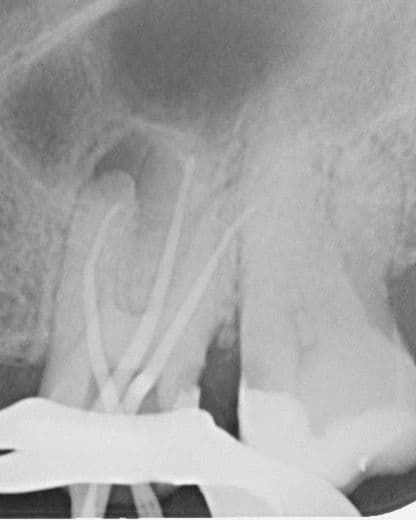

Yaklaşık 9 ay sonra hasta yapılan kontrolde (2024 Şubat) meziobukkal kök ucunda subklinik şekilde seyreden lezyon olduğu görüldü. Ancak hasta mevcut durumda tekrar tedaviyi kabul etmedi (Şekil 3). (Reddetti)

(Şekil 3). 2024 Şubat kontrol meziobukkal kök ucunda periapikal lezyon